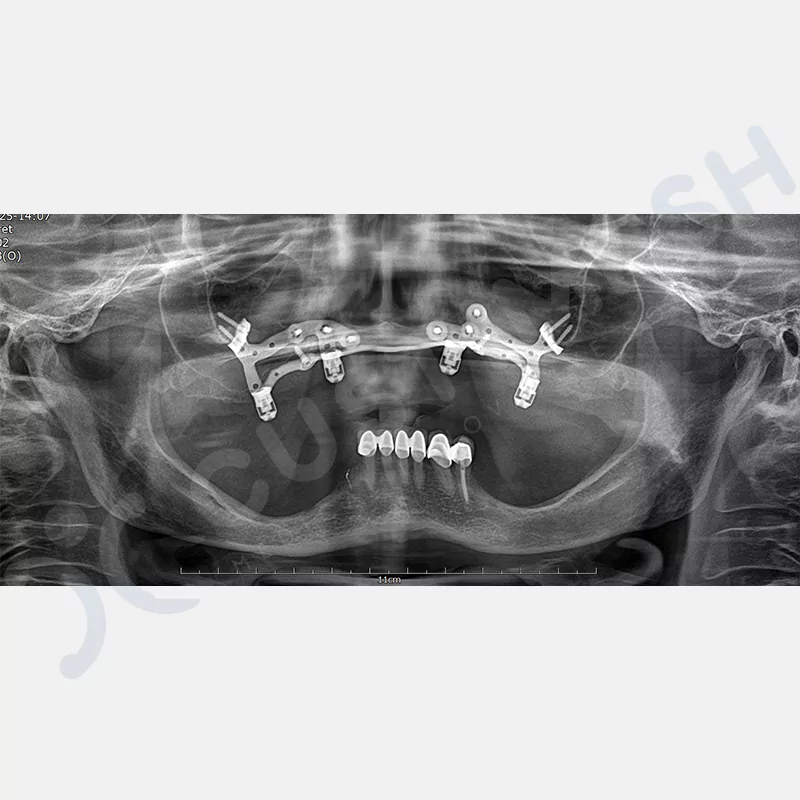

VAKA 1

VAKA 2

VAKA 3

VAKA 4